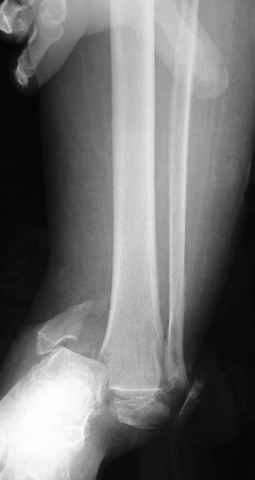

Pilon fracture:

-Появляется ориентир и остов, на чем можно строить восстановление, почему сперва малоберцовую, впервые обьяснили и описали (Pylon type and Ankle fractures) в середине 50х Rienau и Gay.

Восстановливая длину и ротацию малоберцовой кости, затем относительно легче произвести реставрацию остальных элементов перелома дистального эпиметафиза болшеберцовой кости.

где исследования на трупах показали, что малоберцовая кость участвует в стабильности голеностопного сустава, поддерживая наклон тарана (talar tilt) за счет связок. После ознакомления работой Ramsey в ортопедию ввели термин "при переломах голеностопного сустава смещенная

таранная кость следует за малоберцовой костью" т.е. связка не рвется, а тянет таран за собой, поэтому восстановление малоберцовой кости в

первую очередь, затем остальных элементов - стал классическим при лечении данной патолгии. Латеральная колонна (столб), дистальный

конец малоберцевой кости, к нему прикрепляется латеральный суставной фрагмент дистального эпиметафиза большеберцовой кости (как на снимке)

и таранная кость, которые при репозиции малоберцовой кости репонируются автоматически.

Традиционная техники АО, открытая, с точной репозицией суставной поверхности и жесткой фиксацией, из-за серёзных осложнений, которые

заканчивались ампутацией, уходит в прошлое.

Техника сегодня более щадящая, временные несложные аппараты наружной фиксации: Spanning 2 pin ExFix, Traveling traction для лигаментотаксиса, иначе сокращенные мягкие ткани невозможно восстановить позже.